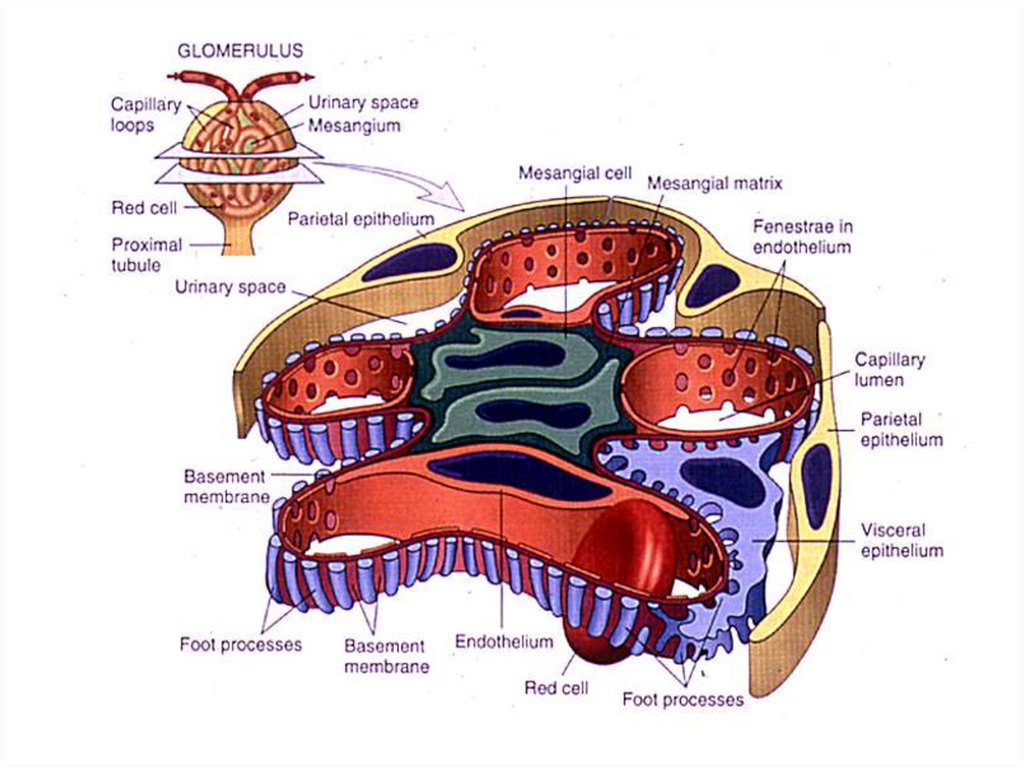

Механизм остро го диффузного гломерулонефрита